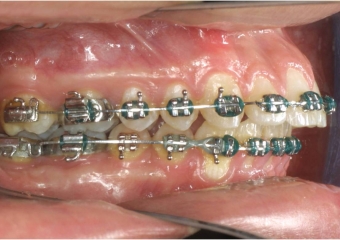

Mordida após cirurgia